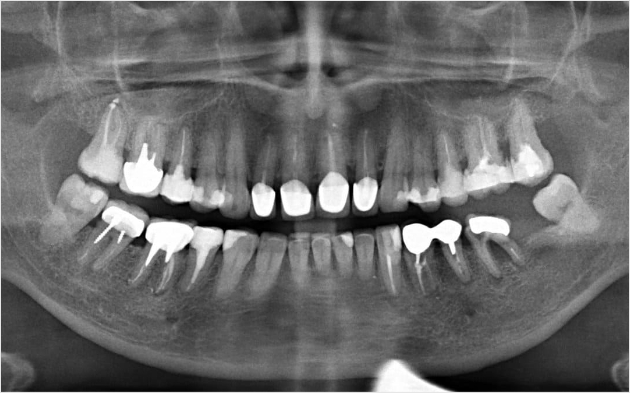

Панорамний знімок зубів

Правильно поставлений діагноз – запорука швидкого, ефективного лікування. Це твердження актуальне для всіх сфер медицини, в тому числі і стоматології. Ставити точний діагноз і виявляти приховані патології фахівцям клініки «Садаф-Дент» допомагає рентгенологія. На знімку буде видно прихований карієс, аномалії розвитку зубів, патології скронево-нижньощелепного суглоба, вогнища запалення в кореневих каналах і ін. Рентген обов’язково проводиться при підозрах на перелом, при наявності зубів, які так і не прорізалися. Робиться знімок і при ортодонтичному лікуванні, дозволяючи стоматолога побачити, наскільки щільно і якісно виконана пломбування кореневого каналу. За допомогою рентгена контролюється процес розвитку запальних реакцій, на підставі чого коригується лікування.

Рентген та діагностикаЦіна

Прицільний внутрішньоротовий знімок (до 3 зубів)200 грн

Ортопантомограма400 грн

КТ верхньої і нижньої щелепи (спец. ціна)950 грн

КТ верхньої щелепи450 грн

КТ нижньої щелепи450 грн

КТ сегмента350 грн

Рентген зубів

Рентген зубів – процедура, не надає негативного впливу на стан організму пацієнта. Тому, якщо в ньому є необхідність, його можна проходити без жодних побоювань і з тією періодичністю, яка потрібна для діагностування і лікування патології. Вагітність – відносне протипоказання. Повідомте про своє становище стоматолога перед процедурою.